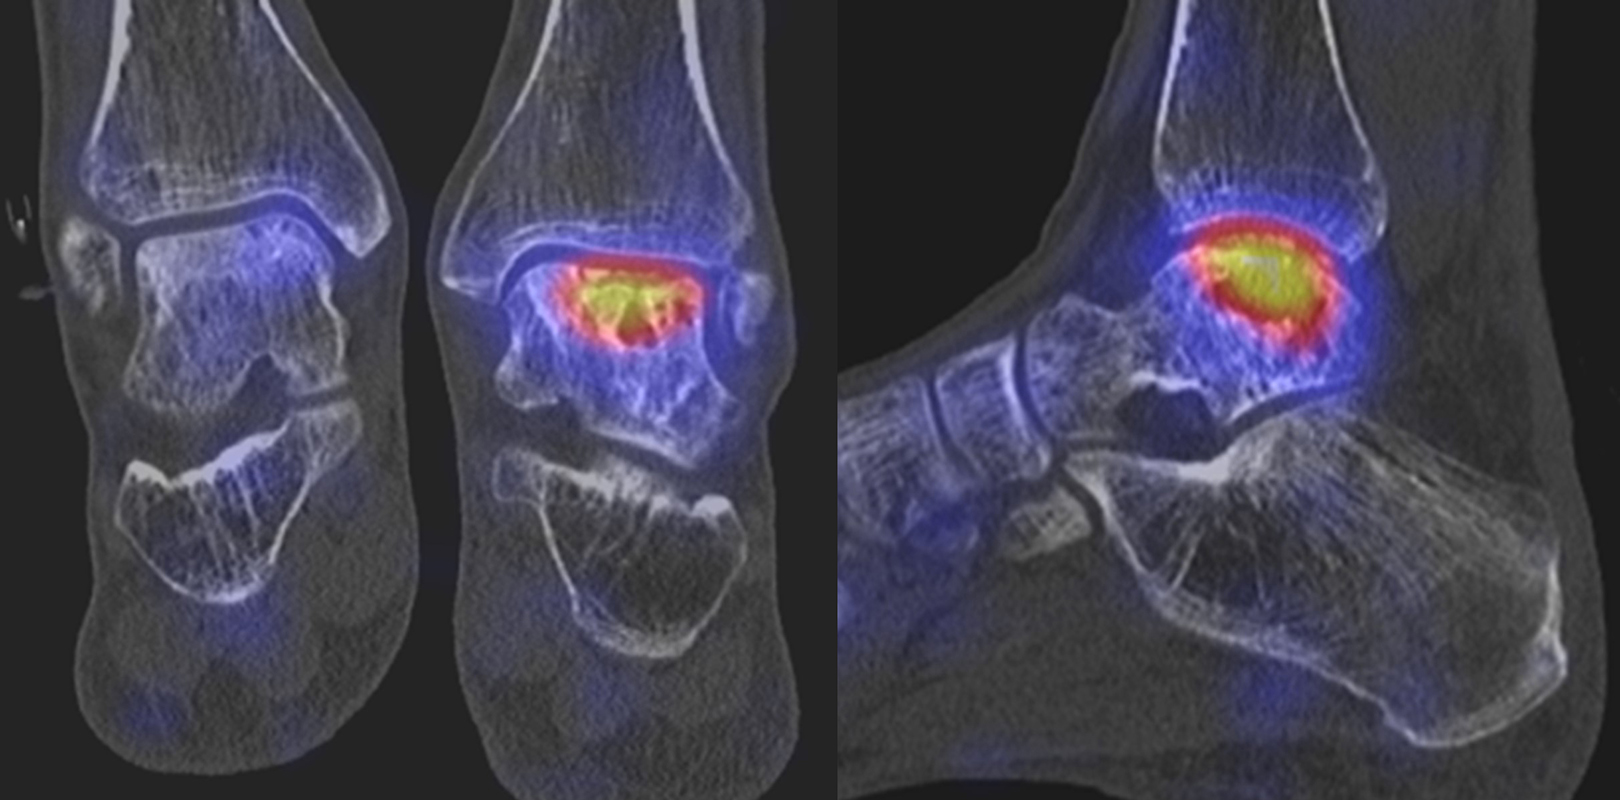

Die Abbildungen 4.2.a bis d zeigen den typischen Aspekt einer talacalcanearen Coalitio. Es besteht nur eine linksseitige, symptomatische Coalitio talocalcaneare (4.2.a und c); das 35 Tage zuvor angefertigte MRT zeigt keine auffälligen Signalveränderungen (4.2.b und d).